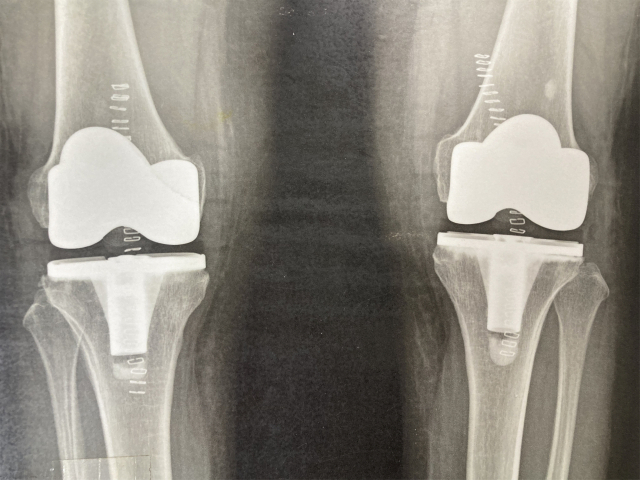

◆ 인공관절 치환술이란?

인공관절 치환술은 손상된 관절을 인공관절로 대체하는 수술적 절차를 말하는데, 주로 무릎, 엉덩이, 어깨, 팔꿈치 등의 관절 기능을 회복시키고 통증을 완화하기 위해 시행한다.

인공관절은 내구성이 높아 오랜 기간에 걸쳐 사용할 수 있으며, 환자 개별적인 상황과 필요에 맞게 설계할 수 있다. 특히 수술 후 회복기간이 비교적 짧아 재활 프로그램을 병행하면 일상으로의 복귀가 빠르다는 장점이 있다.

구재모 센터장은 "인공관절 치환술에서 가장 중요한 것은 수술 후의 안정감"이라고 말한다. 환자의 상태에 정확하게 맞추어 인공관절을 제작해야 하며, 인대와의 밸런스가 잘 맞아야 수술이 제대로 시행되었다고 할 수 있다. 그래서 인공관절 치환술을 받은 모든 환자가 만족하는 것은 아니며 수술 집도의의 숙련도에 따라서 환자의 만족도가 크게 다르게 나타나게 된다.